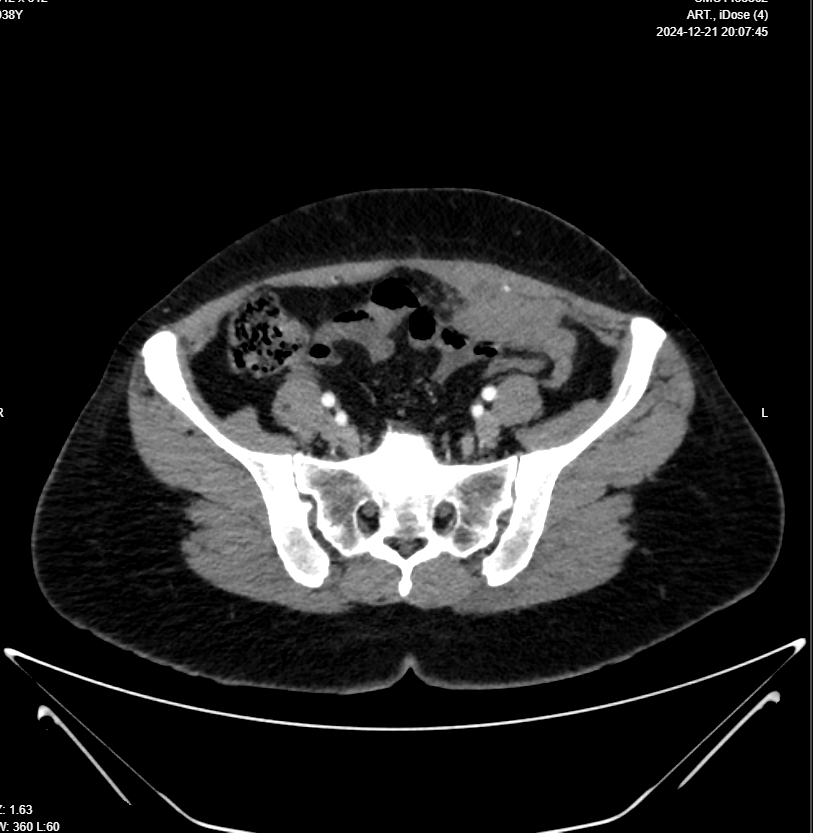

Chest, Abdomen & Pelvic CT With IV Contrast

Clinical data: Malignant LEFT OVARIAN MASS KINDLY FOR PRE RX STAGING

- Evidence of 6 X 4 X 3cm multilocular mass in Lt lower abdomen, arises from Lt adnexa “attached to uterus and Lt ovary”, invades posterior aspect of Lt rectus muscle, in contact with Lt inferior epigastric artery, also in contact with loop of small intestine with no frank invasion, this mass has surrounding fat stranding, which makes it possible to be infection like tubo-ovarian abscess, although malignancy can not be excluded, lab studies and MRI is suggested for further evaluation please.